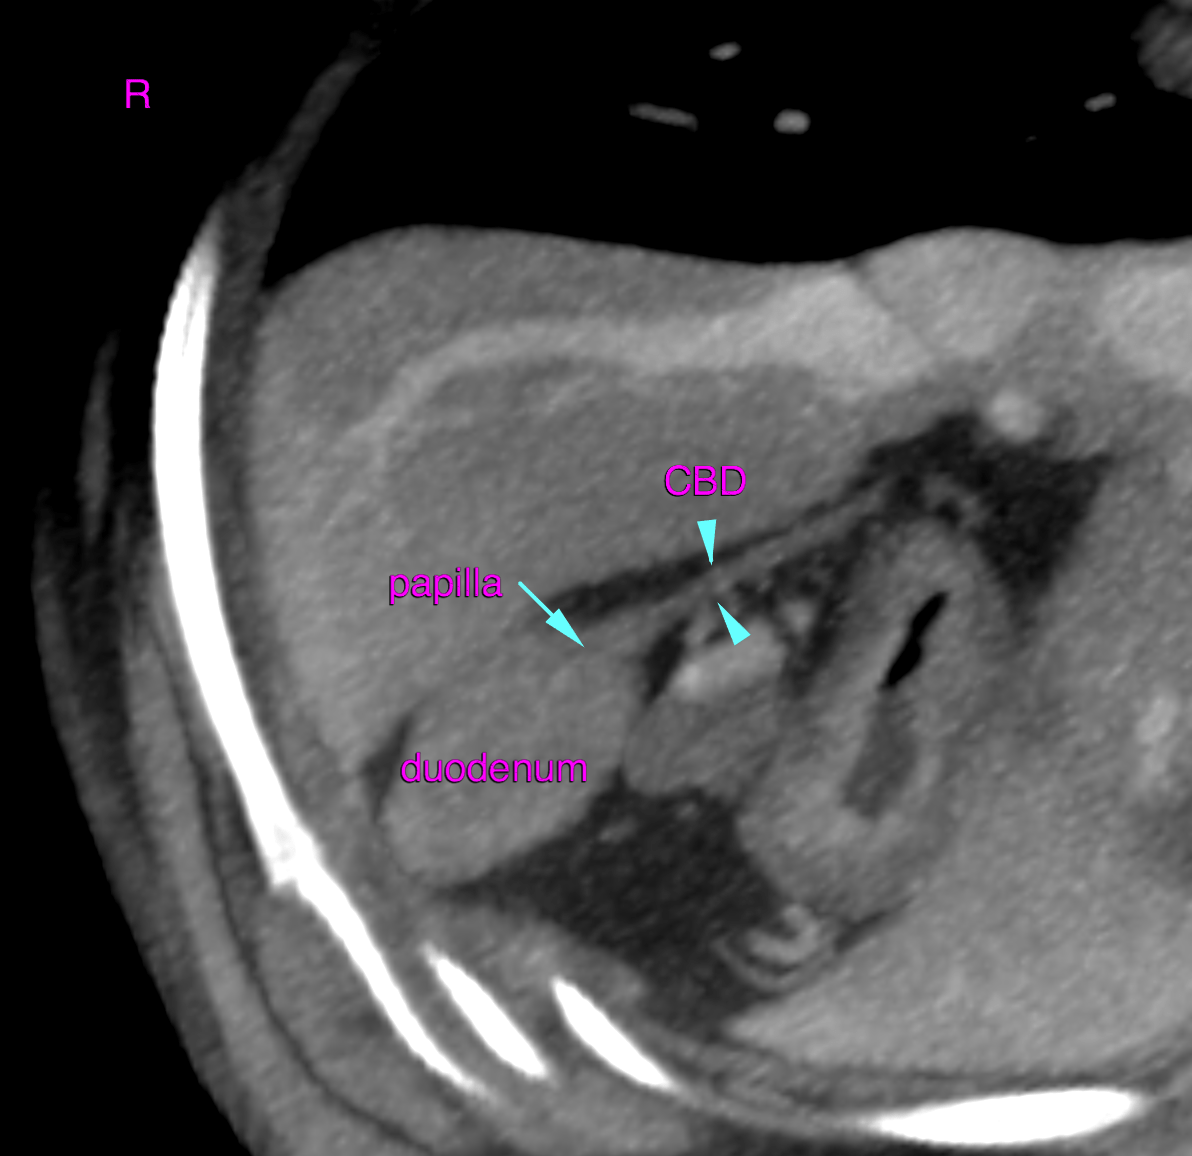

CT – Structurally normal abdomen in a 10 year old MN Dachshund with history of elevated liver enzymes

This 10 year old Dachshund has a history of liver enzyme elevation of at least 6 months duration.

CT of the abdomen – The computed tomographic findings of the liver and remainder of the abdomen are within normal limits.

No evidence of structural pathology within the abdomen